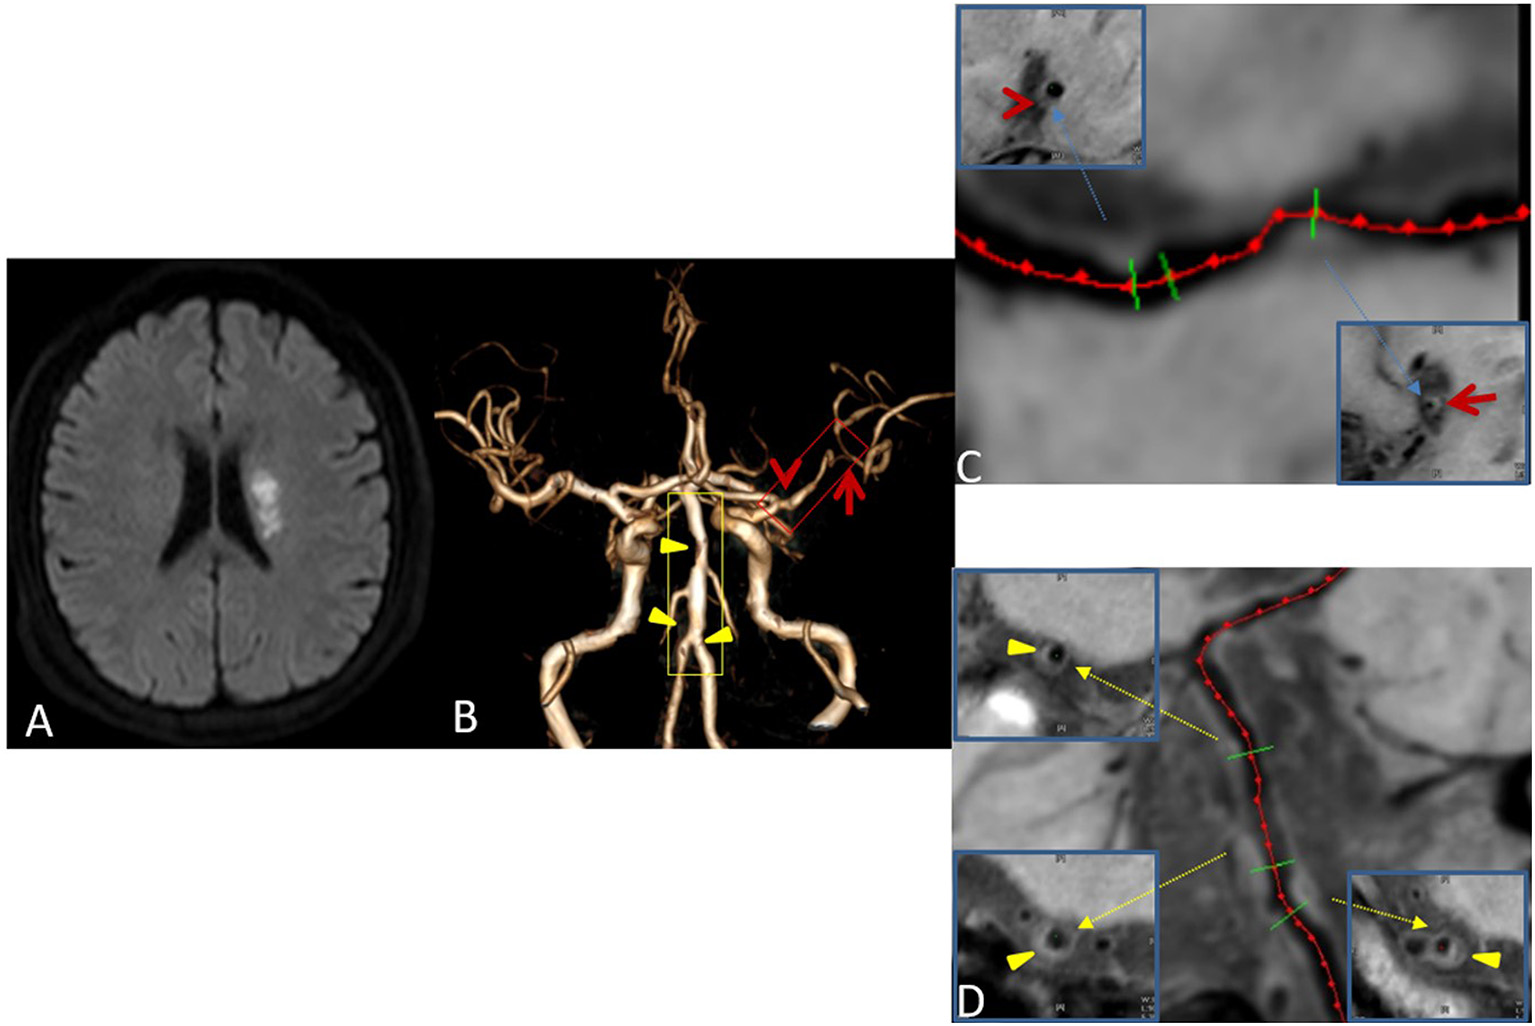

Figure 3

Plaque Classification. Male, 42 years old, presenting with sudden right limb weakness for 8 h. Diffusion-weighted imaging (DWI) shows acute left lateral paraventricular infarction (A). Time-of-flight magnetic resonance angiography (TOF MRA) shows stenosis at two sites in the M1 segment of the left middle cerebral artery (red box) and three sites in the basilar and left vertebral arteries (yellow box) (B). Curved planar reconstruction images show severe stenosis at the distal end of M1 as the culprit plaque (red arrow), and mild stenosis at the proximal end of M1 as an uncertain plaque (red Arrowhead) (C). The three plaques of the basilar artery and left vertebral artery are non-culprit plaques (Yellow triangular arrowheads) (D).

On the basis of the possibility of stroke identified on routine MRI, each plaque was categorized as culprit, uncertain, or non-culprit. If a plaque was the only lesion in the vascular area of the stroke or if it was the narrowest lesion among multiple plaques in the same vascular area of the middle wind, it was categorized as a culprit plaque. If a plaque was not the narrowest lesion in the same vascular area of the stroke, it was categorized as uncertain. If a lesion was not in the vascular area of the stroke, it was categorized as non-culprit (Figure 3). For patients with transient ischemic attack (TIA), plaque classification should be performed if the symptoms can be localized to the corresponding vascular region (21).